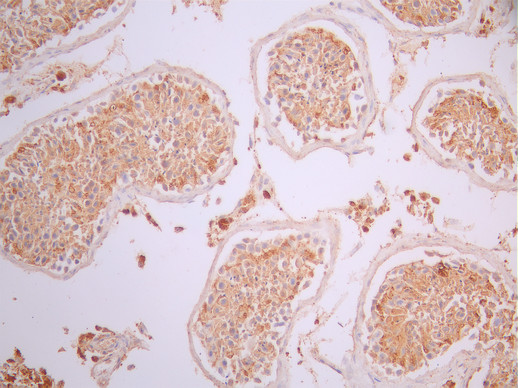

IHC image of CSB-RA017713MA1HU diluted at 1:50 and staining in paraffin-embedded human testis tissue performed on a Leica BondTM system. After dewaxing and hydration, antigen retrieval was mediated by high pressure in a citrate buffer (pH 6.0). Section was blocked with 10% normal goat serum 30min at RT. Then primary antibody (1% BSA) was incubated at 4°C overnight. The primary is detected by a Anti-Human lgG, Fcy Fragment Specific labeled by HRP and visualized using 0.05% DAB.